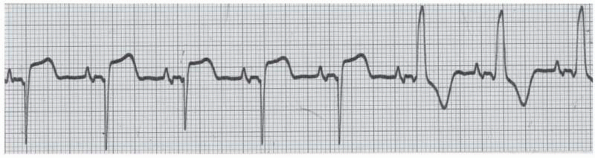

Question 10 of 34

10. Question

Name that rhythm -